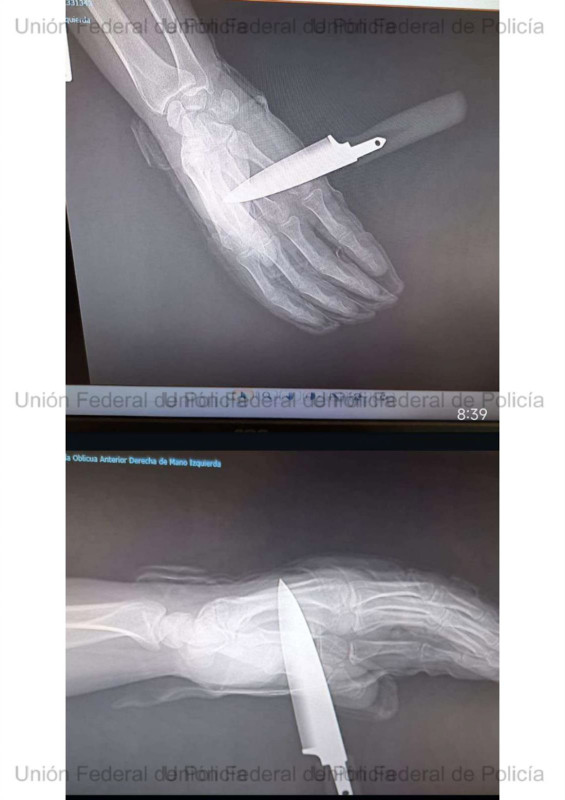

Apuñalan a un agente de la Policía Nacional en Baza durante una intervención por violencia familiar

El chaleco antibalas evitó una tragedia mortal y el policía, herido con un cuchillo en la mano, logró reducir al agresor con ayuda de su compañera